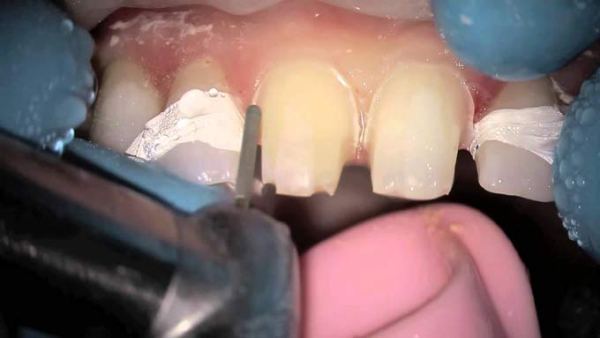

- Непосредственное препарирование – в зависимости от цели, способы обработки зуба будут отличаться между собой. Так, если стачивают жевательную единицу, то воздействуют на верхние бугорки. А при обработке резцов нужны разнонаправленные движения.

Передние зубы стачивают алмазным бором в том случае, если они значительно выступают. В более тяжелых обстоятельствах, сначала создается диагностический макет зубных рядов, и уже после досконального обследования их подпиливают.

Так, при обработке жевательных моляров стоматолог осуществляет аккуратное сошлифовывание верхнего слоя эмали с поверхности бугорков. При спиливании передних резцов осуществляются разнонаправленные движения.

Перед тем как подпилить передние зубы, врач сначала определяет проблемные участки, а также оценивает состояние эмали. Выявить неровности зубных рядов можно при помощи копировальной бумаги, восковой пластины или жидкого аэрозоля. Проблемные участки окрашиваются в более интенсивный цвет.

Зубы, которые сильно выступают, подпиливают при помощи алмазного бора. В тяжелых случаях сначала изготавливают диагностические модели зубных рядов. После оценки их состояния производят диагностическое шлифование.

При подпиливании жевательных зубов нужно плавно счищать эмаль с зубных бугорков. При шлифовании резцов применяют другую методику. Подпиливание происходит с использованием разносторонних движений нижней челюсти относительно верхней.